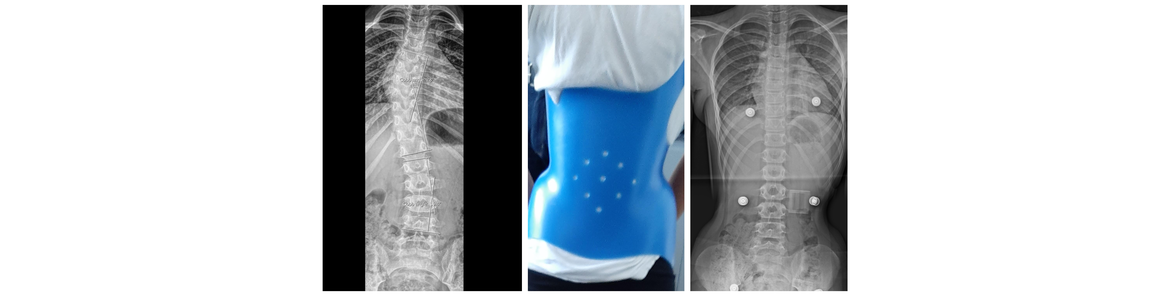

Ραιβοϊπποποδία